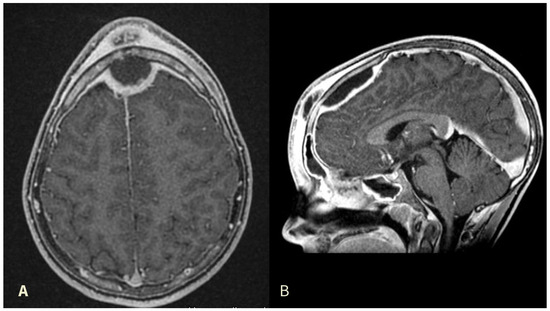

A 12-year-old, Italian male with no comorbidities complained of nasal congestion and headache for one month, who was initially treated by his general practitioner with oral amoxicillin (1 g every 12 h for a week). He presented thereafter to the emergency department clinic with progressively increasing frontal swelling and eyelid edema. He underwent cerebral and head and neck contrast-enhanced CT scan and MRI that revealed a complicated frontal sinusitis with bone erosion of the posterior wall of the frontal sinus and an epidural collection with peripheral rim enhancement at the frontal lobe, suggestive of an epidural abscess with compression of sagittal sinus (Figure 1). He was transferred to our hospital where he received intravenous (IV) vancomycin 40 mg/kg/day, metronidazole 20 mg/kg/day, and ceftazidime 2 g/day. Ophthalmological evaluation excluded orbital complications.

Figure 1. Preoperative contrast-enhanced MRI image revealing subcutaneous forehead swelling and a frontal epidural abscess in axial (A) and sagittal (B) views.